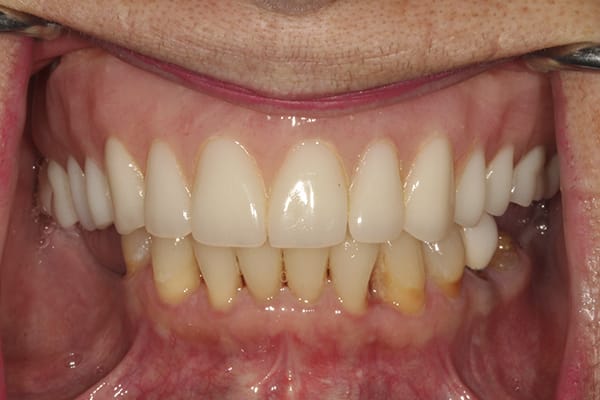

A 72-year-old woman presented with pre-existing dental implants in the approximate positions of Nos. 3, 5, 8, 11, and 14. Because of the patient's age and history of osteoporosis, the surgeon who performed the implant placement had had difficulty locating adequate bone to support the implants. Although the implants were osseointegrated with no clinical signs of mobility, a moderate amount of bone loss around each one was evident. The patient was initially treatment-planned for a crown-and-bridge FP3-style fixed restoration. However, after extensive discussion regarding her concerns, which included a desire for a more esthetically pleasing smile, she opted for a removable RP4-style LOCATOR® bar overdenture restoration (Zest Dental Solutions, zestdent.com), which she would be able to clean and maintain regularly and independently. A vinyl polysiloxane (VPS) impression was made of the implants and a prototype restoration designed. With the prototype used as a guide, a bar framework with four LOCATOR abutments was fabricated. Denture teeth were applied to the framework suprastructure, and the fit of the bar and the tooth arrangement were evaluated intraorally. Upon patient approval, the restoration was finalized and processed using conventional methods. The patient returned for prosthesis placement, and the LOCATOR bar was placed onto the implants. The prosthesis was then placed onto the bar ensuring its stability, and esthetics, phonetics, and occlusion were confirmed.

The RP4-style LOCATOR bar overdenture restoration used in this case provided the patient the esthetics she desired while giving her the ability to remove, clean, and maintain the prosthesis.